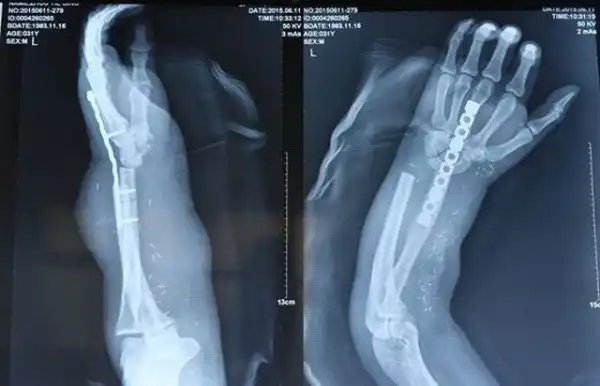

В результате инцидента на производстве мужчине по фамилии Чжоу оторвало кисть. Чтобы не потерять конечность хирургам пришлось пришить ее к лодыжке пациента и восстановить таким образом кровообращение. Затея была рисковая, но сработала - кисть пришили обратно. Правда, период реабилитации будет долгим - пока пациент можеть лишь с трудом шевелить пальцами.